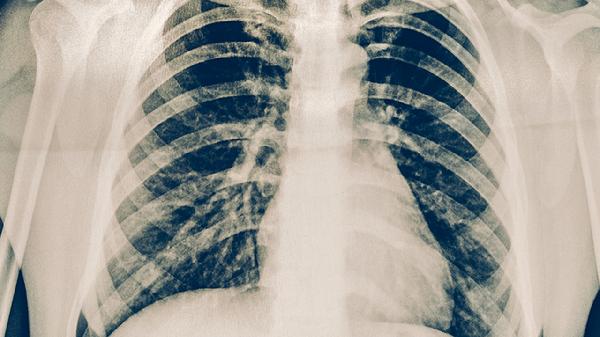

支原體肺炎初期癥狀主要有發(fā)熱、咳嗽、咽痛、頭痛、乏力等。

支原體肺炎初期癥狀與普通感冒或流感有相似之處,但咳嗽往往更為突出和持久。在出現(xiàn)上述癥狀時,特別是劇烈干咳伴發(fā)熱持續(xù)不退,應及時就醫(yī)進行病原學檢查,如血清支原體抗體檢測或核酸檢測,以明確診斷。確診后需在醫(yī)生指導下規(guī)范使用大環(huán)內(nèi)酯類、四環(huán)素類或氟喹諾酮類等抗菌藥物進行抗感染治療,切忌自行用藥。治療期間應居家休息,保持室內(nèi)空氣流通,飲食宜清淡、富含優(yōu)質(zhì)蛋白和維生素,避免前往人群密集場所,咳嗽或打噴嚏時注意禮儀,以促進康復并防止疾病傳播。